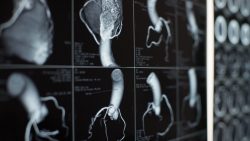

Four valves regulate blood flow through your heart:

• The tricuspid valve regulates blood flow between the right atrium and right ventricle.

• The pulmonary valve controls blood flow from the right ventricle into the pulmonary arteries, which carry blood to your lungs to pick up oxygen.

• The mitral valve lets oxygen-rich blood from your lungs pass from the left atrium into the left ventricle.

• The aortic valve opens the way for oxygen-rich blood to pass from the left ventricle into the aorta, your body’s largest artery.